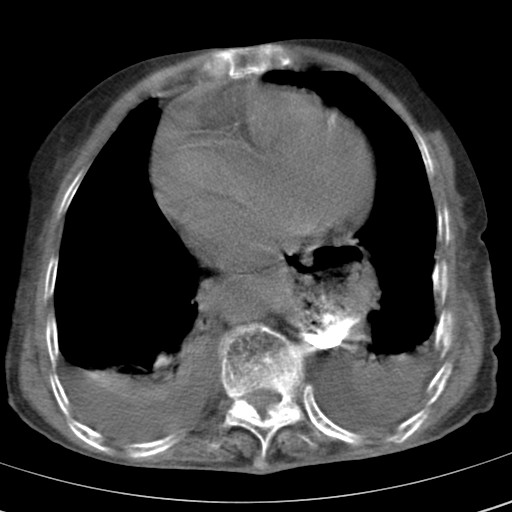

标题: CT21467:女,93岁,摔伤后检查。

女,93岁,摔伤后检查。

右肺炎症,心功能不全伴双侧胸腔积液,右下肺膨胀不全,食管裂孔疝,冠脉钙化,心包少量积液,左侧肋骨骨折,请上传骨窗.

创伤性湿肺,双侧胸腔积液。可能有食管裂孔疝,进一步检查。骨折有无根据自己的机器及片子再仔细看吧。

右侧锁骨\\肩胛骨骨折、右侧湿肺,心功能不全伴双侧胸腔积液,右下肺膨胀不全,左膈破裂或食管裂孔疝,冠脉钙化,心包少量积液,请上传骨窗.

右肺炎症,心功能不全伴双侧胸腔积液,右下肺膨胀不全,食管裂孔疝,冠脉钙化,心包少量积液,左侧肋骨骨折,右肩甲骨粉碎性骨折。93岁,高寿哇!

右肺炎症,心功能不全伴双侧胸腔积液,右下肺膨胀不全,食管裂孔疝,冠脉钙化,心包少量积液,左侧肋骨骨折,右肩甲骨粉碎性骨折。